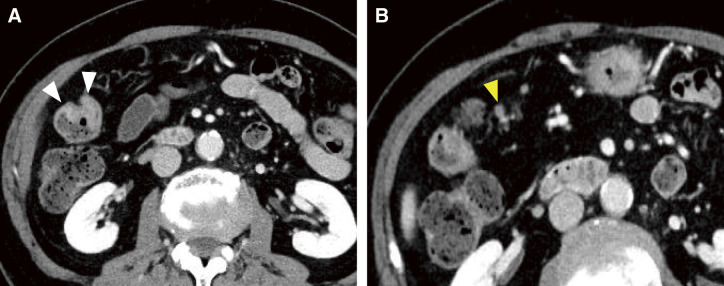

Case presentation: An 83-year-old woman was diagnosed as having advanced colorectal cancer in the transverse colon by lower gastrointestinal endoscopy, and biopsy results revealed moderately differentiated adenocarcinoma. Contrast-enhanced computed tomography showed a tumor located near the hepatic flexure and an enlarged lymph node near the tumor. No distant metastasis was observed, and the preoperative diagnosis was cT3N1aM0 cStage IIIb cancer. Immunohistochemical analysis of the biopsy specimen suggested deficient mismatch repair. During the wait for surgery, the patient was urgently hospitalized due to severe dehydration. After her general condition improved, 38 days after the biopsy, we performed laparoscopic resection of the partial ascending and transverse colon with D3 lymph node dissection. The tumor noted preoperatively was not present in the specimen, and intraoperative endoscopy revealed no tumor on the anorectal side. Additional ileocecal resection was performed, but no tumor was found in the specimen, and another intraoperative endoscopy was performed, which revealed a discolored scar near the anal margin. We determined that tumor loss or morphological change had occurred, so after additional resection of the same area, ultimately, an extended right hemicolectomy was performed. Histopathological diagnosis was pT0N0M0 pStage0 cancer with no residual tumor. The patient has progressed without recurrence at 1 year after the operation.